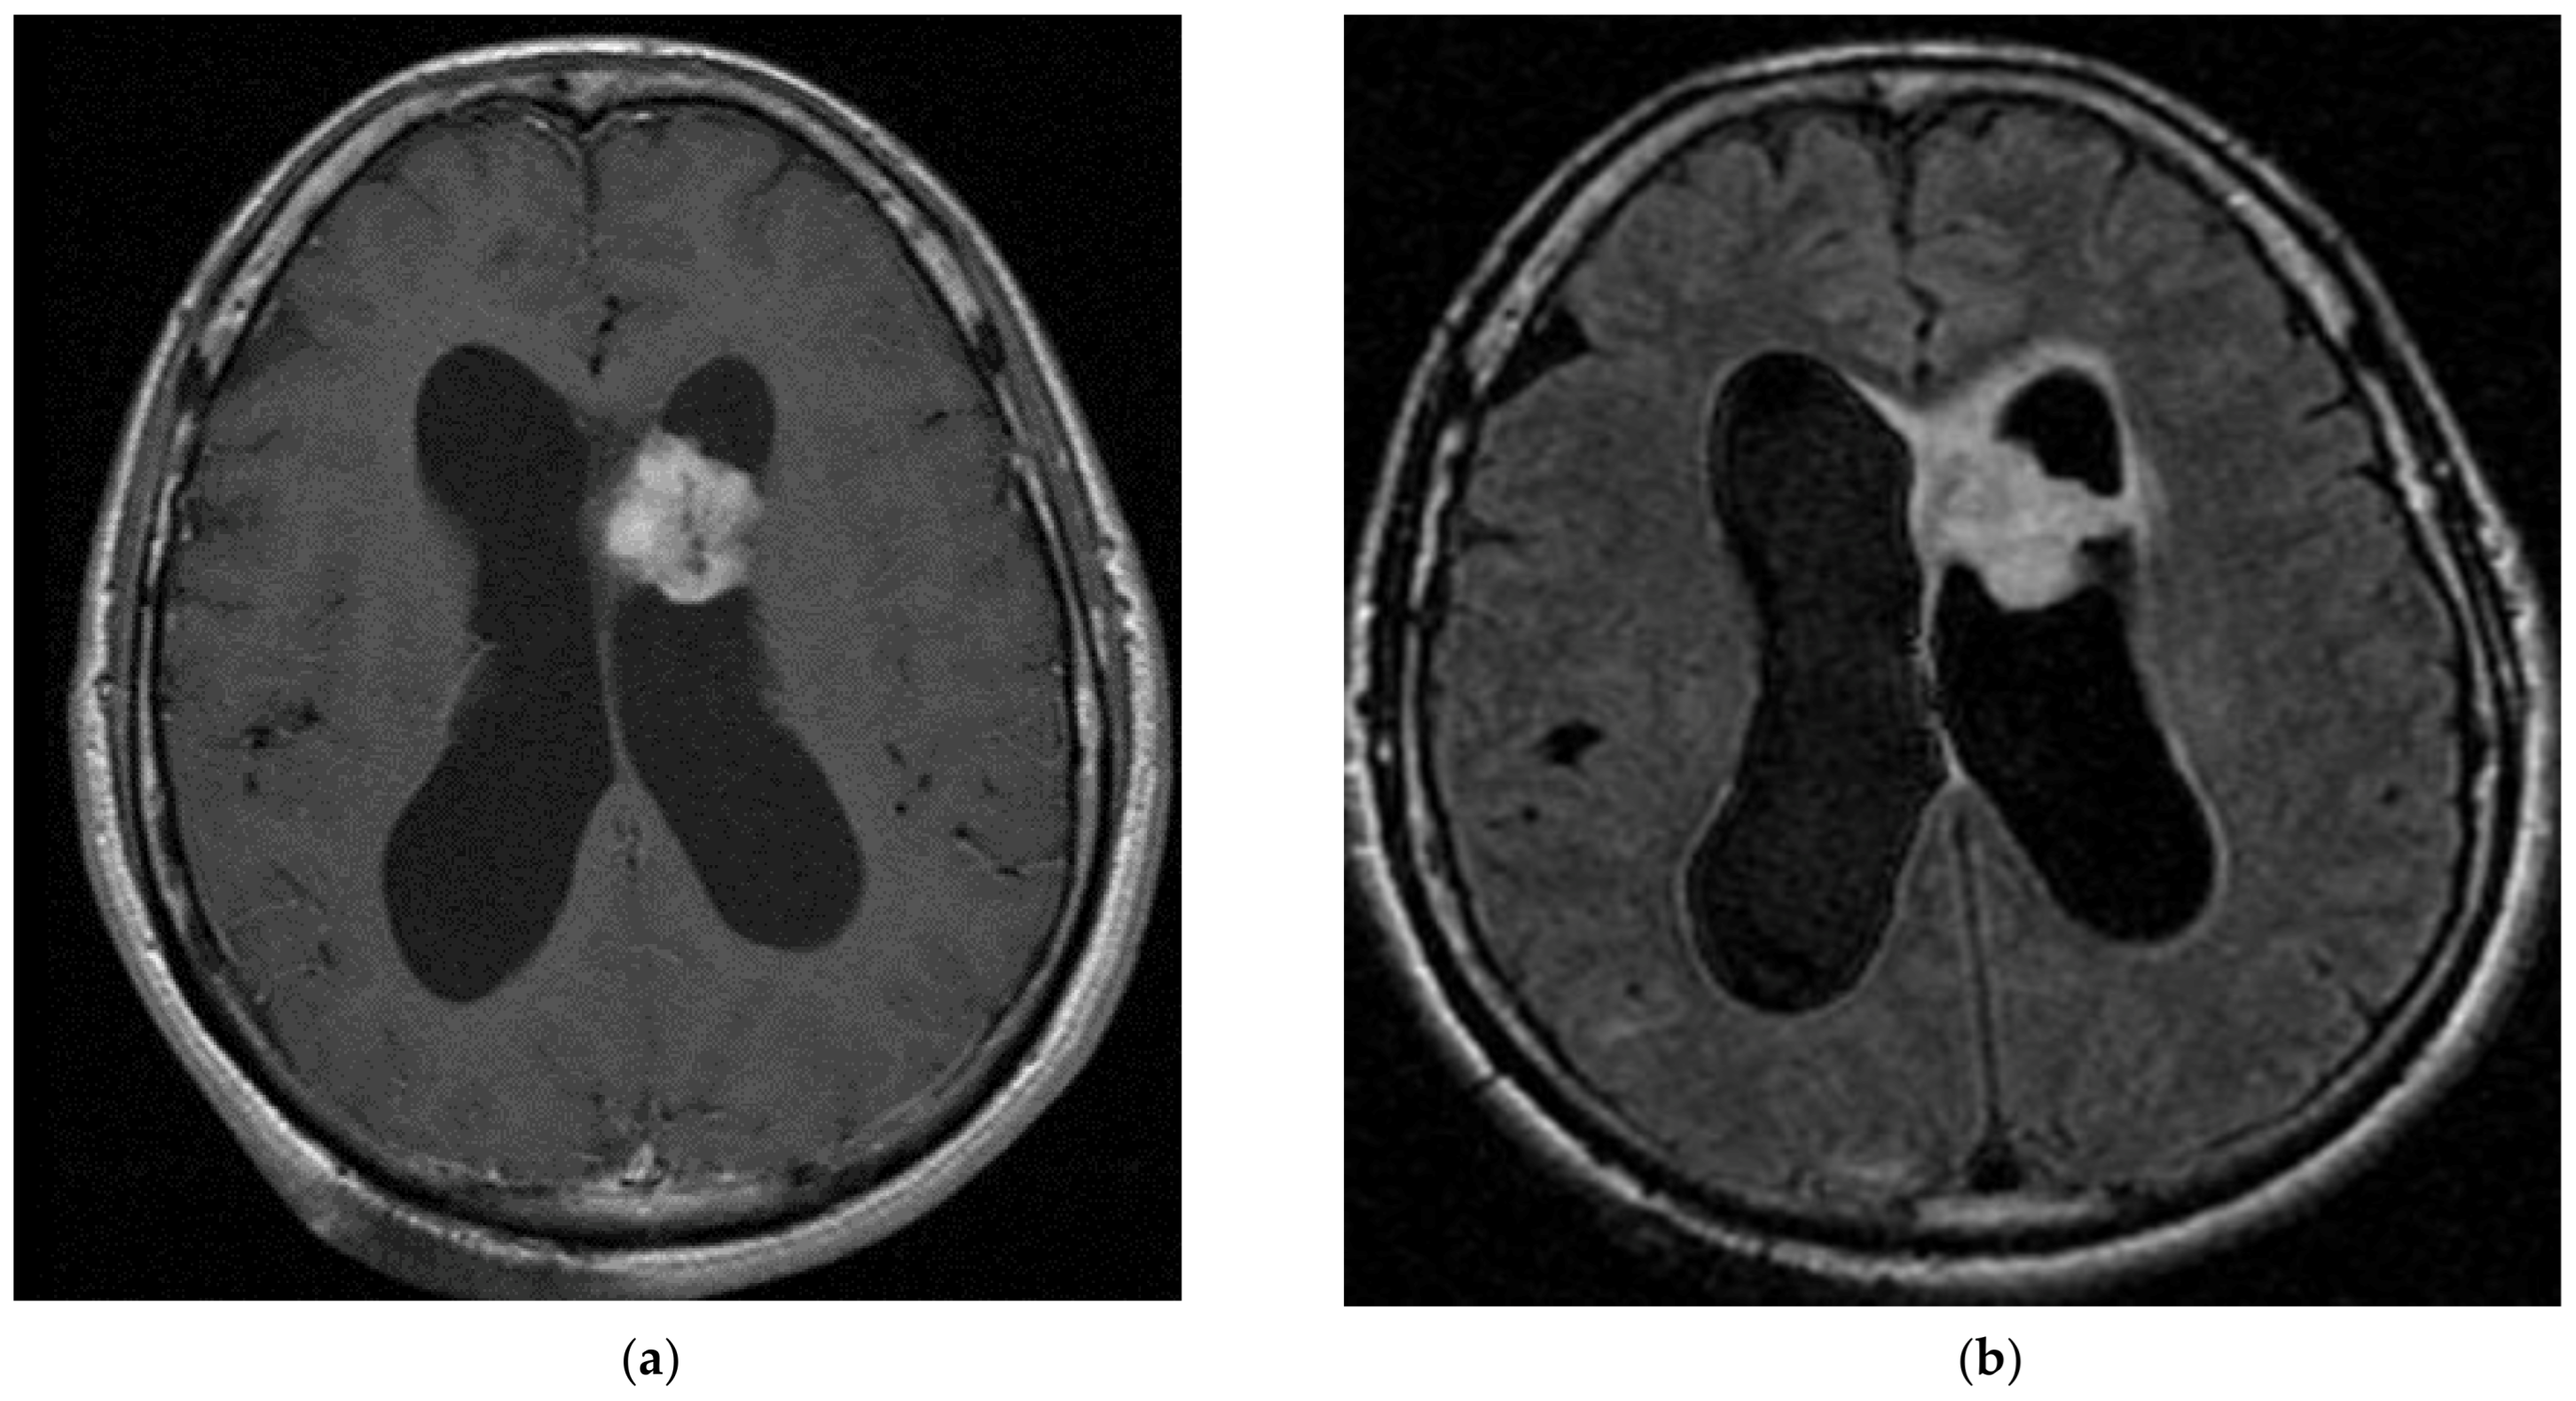

3.5. Subependymal Giant Cell Astrocytoma (SEGA)

- Jóźwiak, S.; Nabbout, R.; Curatolo, P. Management of subependymal giant cell astrocytoma (SEGA) associated with tuberous sclerosis complex (TSC): Clinical recommendations. Eur. J. Paediatr. Neurol. 2013, 17, 348–352. [Google Scholar] [CrossRef] [PubMed]

- Jóźwiak, S.; Mandera, M.; Młynarski, W. Natural History and Current Treatment Options for Subependymal Giant Cell Astrocytoma in Tuberous Sclerosis Complex. Semin. Pediatr. Neurol. 2015, 22, 274–281. [Google Scholar] [CrossRef]

- Roth, J.; Roach, E.S.; Bartels, U.; Jóźwiak, S.; Koenig, M.K.; Weiner, H.L.; Franz, D.N.; Wang, H.Z. Subependymal giant cell astrocytoma: Diagnosis, screening, and treatment. Recommendations from the International Tuberous Sclerosis Complex Consensus Conference 2012. Pediatr. Neurol. 2013, 49, 439–444. [Google Scholar] [CrossRef]